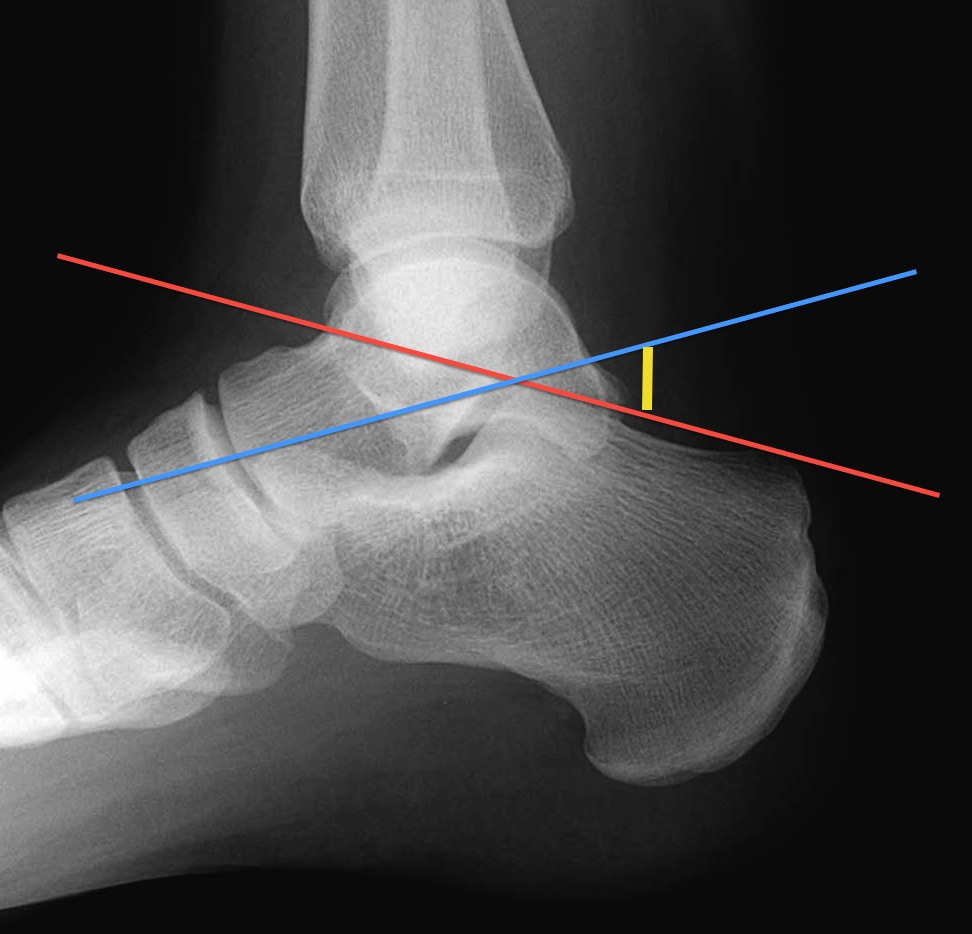

using the lateral view, angle (yellow line) formed by line drawn from posterosuperior calcaneal tuberosity ( RID2962 ) to tip of the posterior facet of the subtalar joint (red line) and line from tip of posterior facet through superior margin of anterior process of calcaneus (blue line).

if < 20 degrees then compression of superior aspect of bone, fracture ( RID4650 ) of calcaneus or of posterior facet

how to draw the boehler angle